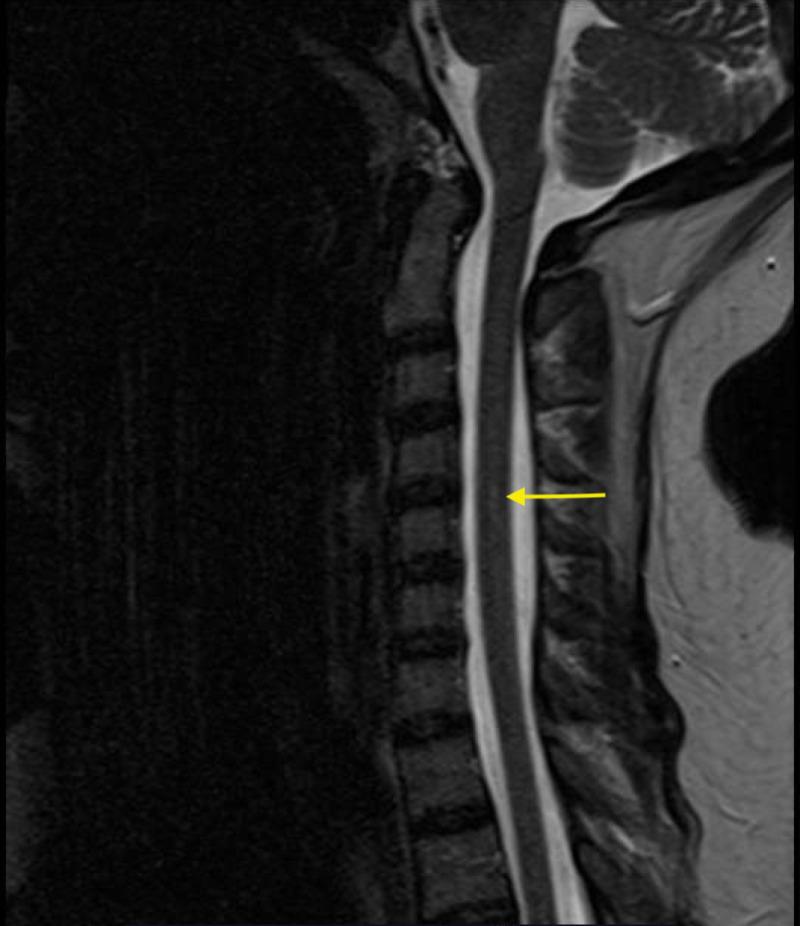

Nitrous oxide, primarily used in the medical field and in the food industry, can cause symptoms of euphoria and analgesia. Recreational use of nitrous oxide is rising, as are reports of its adverse effects, including neurologic complaints secondary to an evoked vitamin B12 deficiency. We outline a case of a patient presenting with several neurologic symptoms and found to have myelopathy secondary to vitamin B12 deficiency in the presence of prolonged recreational nitrous oxide use.

一氧化二氮主要用于医疗领域和食品工业,可引发欣快感和镇痛症状。一氧化二氮的娱乐性使用呈上升趋势,其不良反应的报告也在增加,包括继发于维生素B12缺乏引起的神经症状。我们概述了一例患者,该患者出现多种神经症状,在长期娱乐性使用一氧化二氮的情况下,被发现患有继发于维生素B12缺乏的脊髓病。